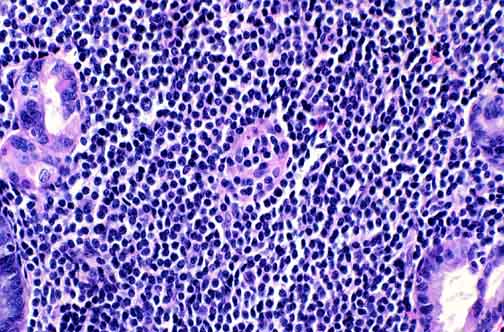

A higher power view of a lymphoepithelial lesion. Note that most of the cells are about the size of benign small lymphocytes. Nuclear contour varies from oval to irregular to occasionally cleaved. Some cells in some cases may have modest amounts of cytoplasm keeping the nuclei are arm's length from each other. Such cells may be called "monocytoid".

Some lymphoepithelial lesions from another maltoma.